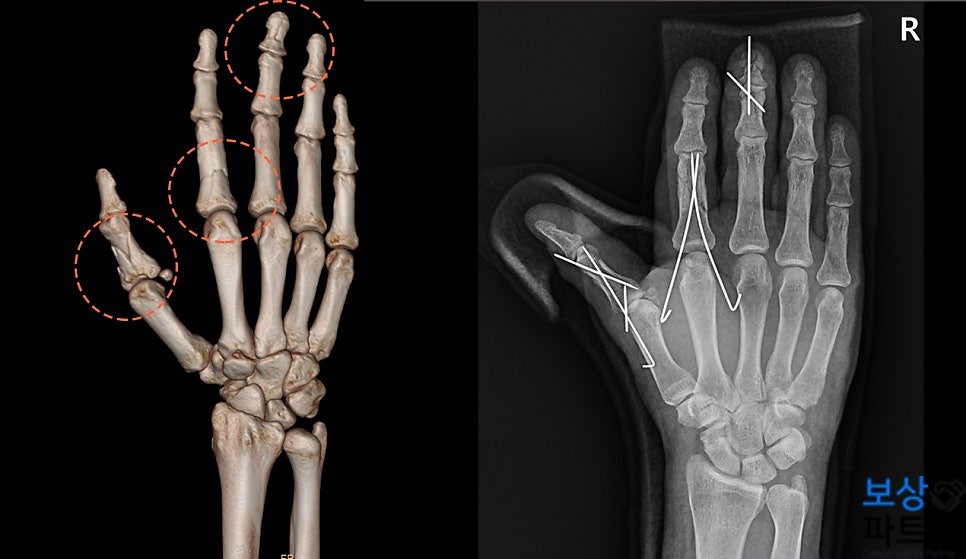

40대 후반의 피해자께서는 현장 업무 중, 기계 장비에 엄지, 검지, 중지가 눌리면서 외상을 입으셨습니다.

진단명 (분류번호) :

엄지손가락 근위지골 골절 (S62520) 제2 손가락 근위지골 골절 (S62620) 제2 수지 신전건 부분파열 (S6630) 제3 손가락 중지골 경부, 원위지골 골절 (S62630, S62640) 위 자료와 같이 재해자께서는 3개의 손가락에 골절상을 입으셨는데요.

안정적인 골유합을 위해 도수정복 및 경피적 핀고정술 시행했으며, 힘줄 파열에 대해 신전건 봉합술도 받게 되었습니다. 이 사고는 근무 중 발생한 재해였으므로 산재 신청이 무사히 승인되었고, 이후 요양급여(치료비) /휴업급여(통원 기간 동안 평균임금의 70%) 를 수령하실 수 있었습니다.